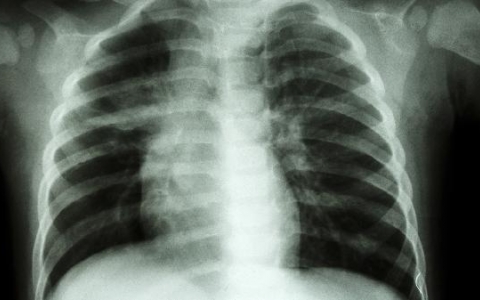

胸腔积液是什么原因造成的

胸腔积液可能是外伤、胸膜炎、肺炎、肺结核、肺肿瘤等原因造成的。建议及时就医治疗。1、外伤:如果受到直接或者是间接暴击,会导致肺部毛细血管破裂出血,不及时处理可能

肺结核病人哪个阶段具有传染性

肺结核病人在传染性最强的阶段通常是疾病的活跃期。这个阶段,病人的体内结核菌数量较多,且容易通过空气传播给他人。尤其是在病人咳嗽、打喷嚏或大声说话时,细菌会随着飞